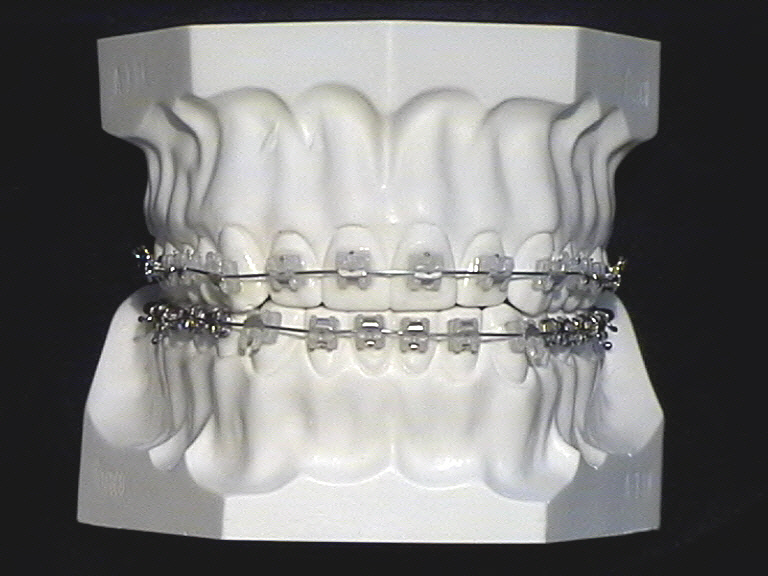

Mit fest sitzenden Behandlungsmitteln können Zähne in alle Richtungen gezielt bewegt werden; auch „körperlich“, d. h., Zahnkrone und Wurzel werden parallel im Kiefer verschoben. Die Bandbreite der festsitzenden Behandlungsapparaturen ist sehr vielfältig. Am meisten bekannt ist die sogenannte Multibandapparatur, welche es in verschiedenen Ausführungen gibt.

Selbstligierend heißt, daß das Bracket selbst ein Schließmechanismus beherbergt. Also keine zusätzlichen Drähte oder Gummiligatuen angebracht werden müssen, um den Drahtbogen im Bracket festzuhalten. Das Keramikbracket ist eine Alternative zum Metallbracket, wenn eine etwas unauffälligere Variante gewünscht ist.